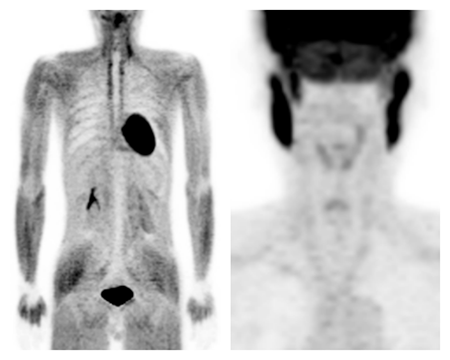

PET検査を受けられる方へ

PET検査を受けるときは、ブドウ糖の代謝状態を正確にとらえるために検査前6時間は絶食をしていただきます。水や緑茶などは飲んでもかまいませんが、ジュースやスポーツドリンク、飴やガム等の糖分を含むものは禁止です。

血糖値が高くなると全身の筋肉に薬が集まり病変が分かりにくくなります。

右図 おしゃべりによる咀嚼筋への集積